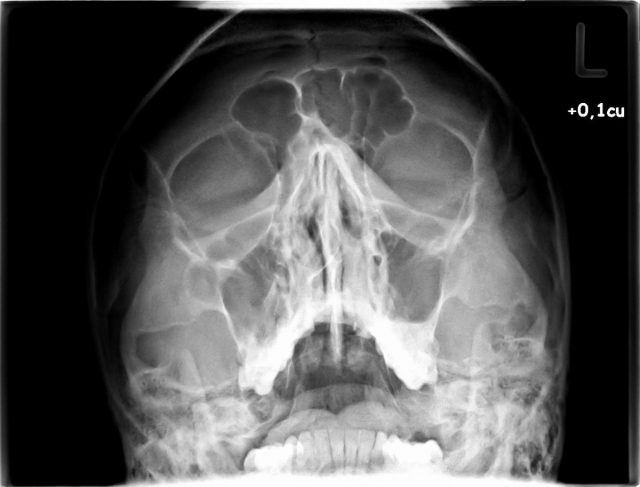

Imagen waters

WATERS

Traumatismo de tercio medio facial y fosas

nasales

El tabique nasal

óseo debe observarse sin rotación.

Debe apreciarse la

colimación estricta